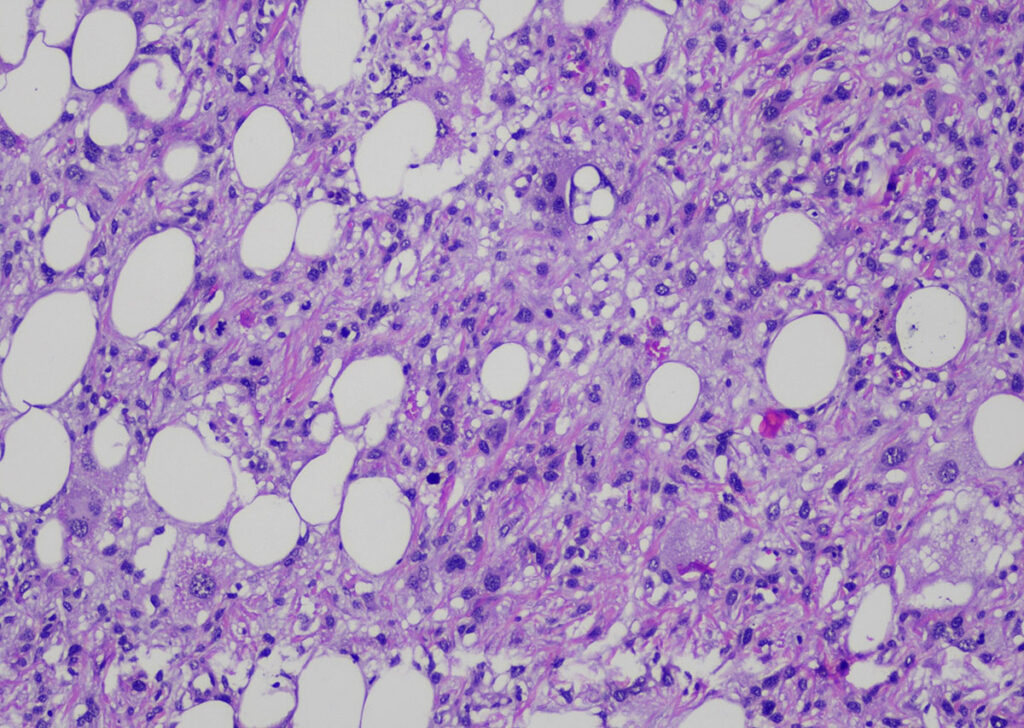

Nelle cavie, predominavano i tumori mesenchimali del (sotto-)cute. Sono stati diagnosticati 508 tumori mesenchimali in totale, di cui 365 benigni e 143 neoplasie classificate come maligne. I tumori sono stati suddivisi in 325 lipomi, 13 fibromi, 13 fibrolipomi e 6 emangiomi. Sono stati diagnosticati altri 8 tumori benigni. Inoltre, sono stati sottoposti a screening 80 sarcomi (non è stato possibile determinare con certezza la popolazione cellulare di origine). Sono stati diagnosticati 29 fibrosarcomi, 24 liposarcomi (Fig. 4) e 10 altre neoplasie mesenchimali maligne.

Fig. 4: Liposarcoma (colorazione HE, ingrandimento 100x)

Fonte: Laboklin